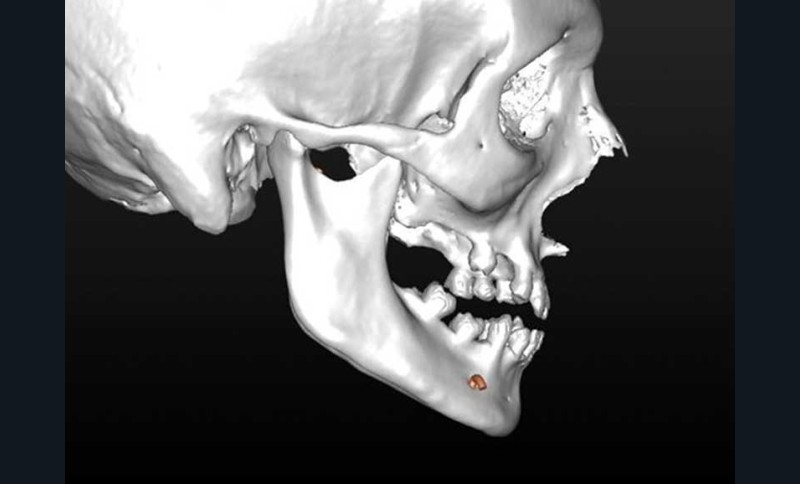

– élaboration des images 3D en isolant des différents constituants anatomiques : crâne et maxillaire, mandibule, dents, dispositifs d’orthodontie, implants endo-osseux et prothèses conjointes éventuelles, etc.

L’enregistrement des classiques modèles en plâtre (en occlusion corrigée de Classe 1) à l’aide d’un scanner conventionnel (format DICOM) ou par empreinte optique (format STL) est ensuite intégré au squelette dento-squelettique ; étape désignée « matching des modèles ».

Rendue possible par la visualisation 2D et 3D interactive des données du patient, elle constitue la première « phase clinique » du processus numérique (flux numérique). Le chirurgien peut aisément visualiser les rapports des bases squelettiques et l’occlusion pathologique, tandis que la sélection interactive de coupes natives (axiales) ou reconstituées (coronales, frontales, sagittales) favorise la compréhension de la…